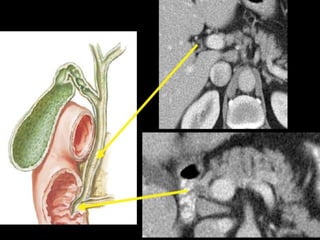

Gallbladder :

 lies in a fossa on the visceral surface of the liver to the right of

the quadrate lobe.

 It stores and concentrates bile, which enters and leaves through

the cystic duct. The cystic duct joins the common hepatic duct

to form the common bile duct.

3/22/2024 27